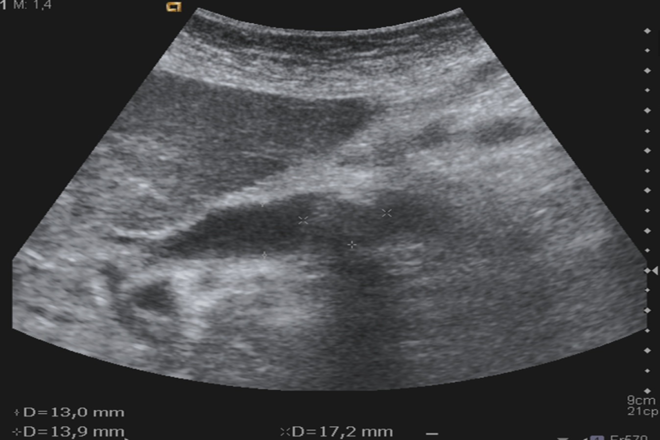

Pancreatitis aguda: Enfermedad frecuente con etiología múltiple, se debe principalmente a litiasis biliar o a alcoholismo crónico. La ecografía abdominal constituye la primera técnica de imagen en la evaluación inicial de una pancreatitis aguda, debiendo realizarse en las primeras 24 h. Tiene importancia en el diagnóstico de la pancreatitis aguda, pero adquiere relevancia en el establecimiento de su etiología, siendo más sensible que la tomografía axial computarizada o la resonancia magnética en el diagnóstico de litiasis biliar. La pancreatitis aguda se presenta, la mayoría de las veces, como un aumento difuso y generalizado del tamaño del páncreas, junto con límites y contornos más imprecisos y disminución de la ecogenicidad del órgano. En la forma edematosa el parénquima es uniforme y homogéneo, aunque hipoecogénico con respecto al parénquima normal. En las formas más graves se pueden observar áreas intraparenquimatosas de carácter quístico, indicativas de la existencia de necrosis o hemorragia. Los resultados técnicos de la exploración mejoran 48 h después del episodio agudo. La exploración ecográfica desempeña un papel importante para monitorizar la evolución: resolución, formación de seudoquistes o pancreatitis crónica. Los hallazgos ecográficos en la pancreatitis aguda pueden clasificarse por su distribución (focal o difusa) y por la severidad (leve, moderada y grave). La pancreatitis focal, que consiste en un aumento de tamaño focal del páncreas. Se localiza generalmente en la cabeza, y es más frecuente en pacientes alcohólicos y con historia previa de pancreatitis o dolor, lo que demuestra que las pancreatitis focales tienden a ocurrir en el contexto de una pancreatitis crónica. En una pancreatitis difusa el páncreas es hipoecogénico respecto al hígado normal y está aumentado de tamaño. A medida que la inflamación es más severa son más evidentes la disminución de la ecogenicidad y el aumento de tamaño debidos al mayor contenido líquido en el intersticio. La ecografía no permite distinguir, como lo hace la tomografía axial computarizada, entre pancreatitis necróticas y no necróticas. Las manifestaciones extrapancreáticas consisten en colecciones líquidas y edema a lo largo de los diferentes planos de partes blandas, y, en general, se ven en los casos severos. Los cambios en las partes blandas peripancreáticas se ven como bandas hipoecogénicas adyacentes al páncreas o rodeando el sistema venoso portal. Las colecciones líquidas extrapancreáticas ocurren dentro de las 4 semanas desde el inicio de la inflamación aguda. Se emplea el término «seudoquiste» cuando se desarrolla una colección líquida con la pared bien definida, que permanece en exploraciones seriadas durante un intervalo de al menos 4 semanas desde el inicio de la inflamación aguda. Se necesitan aproximadamente de 4 a 6 semanas para que una colección líquida se circunscriba con una pared de colágeno y tejido de granulación vascular. Los seudoquistes ocurren en un 10-20% de los pacientes con pancreatitis aguda y en un 25-40%de los pacientes con pancreatitis crónica, y es la lesión quística más frecuente del páncreas. En la fase inicial pueden existir ecos internos y contornos peor definidos, al no estar aún organizado el quiste. Posteriormente la forma es más o menos ovoidea, con contenido anecogénico y con una pared mejor definida.